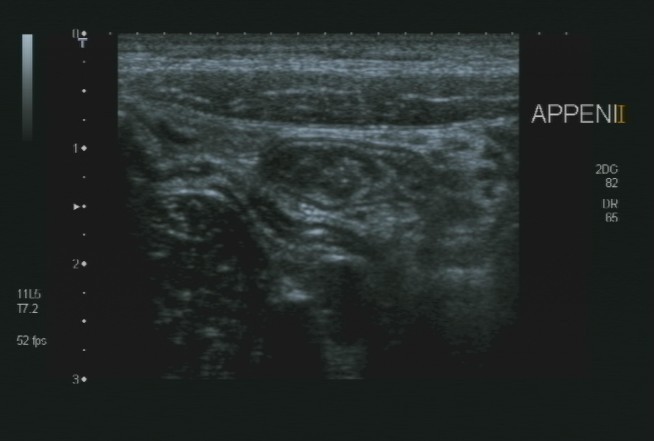

Lo studio medico privato del Dottor Patrizio Stornelli è ad Avezzano è dotato di un'attrezzatura ecografica moderna. Oltre alla ecografia addominale dei parenchimi, si esegue l'ecografia gastroenterolgica ed in particolare l'ecografia del tenue, che consente la diagnosi ed il follow-up particolaremente dei paziente con malattia di Crohn, ma anche l'ecografia del colon. Grazie a questo approccio è possibile scansionare interi segmenti del colon con particolare riguardo alla patologia diverticolare ma anche di indiduare l'appendice e di porre diagnosi di certezza di eventuale appendicite acuta.